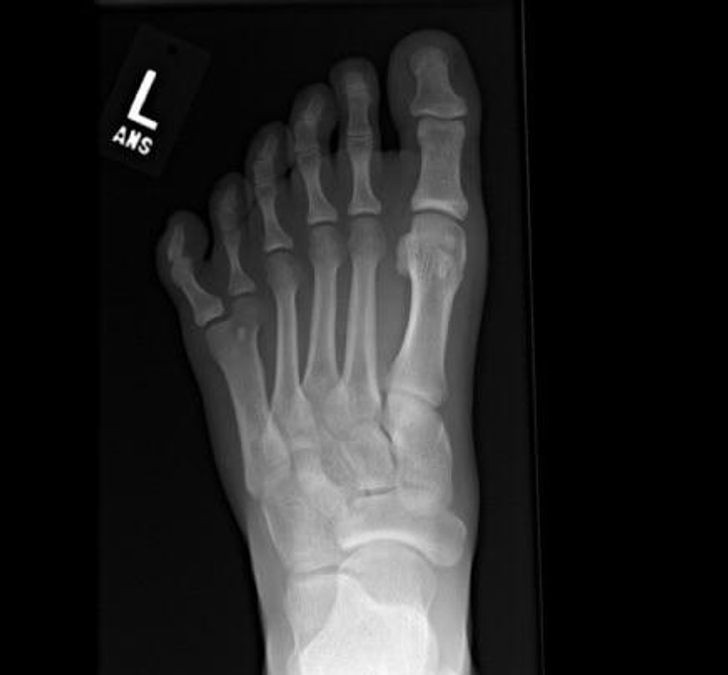

8. Haluks widoczny na prześwietleniu

8. Haluks widoczny na prześwietleniu © Encantalasmontaas / Reddit